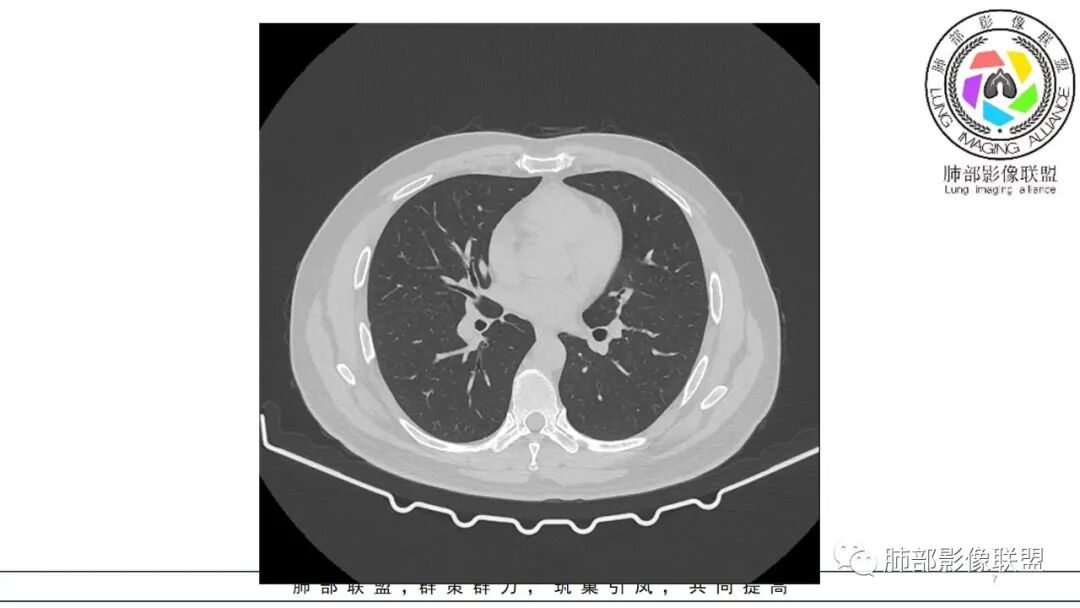

中年男性,咳嗽咳痰低热三天。右肺中叶、下叶条片状高密度影,局部边缘有晕,可见卫星灶。双肺另见多发小结节。考虑炎性肉芽肿,PC,鉴别GPA

中年男性,咳嗽咳痰伴发热3天,有鼻窦炎、 中耳炎病史,血沉、 CRP 增高,中性粒稍高。

双肺多发实性小结节,边清,多位于胸膜下。右肺中叶不规则实变影,沿支气管血管束走行,似有跨叶。

分布有点怪异,多灶,胸膜下,外周小结节,中叶病灶跨叶,似乎与支气管垂直,不是平行关系,蠕虫样,周围渗出,内部坏死,血道来源?肿瘤不能解释,感染性肉芽肿炎不像,中耳炎病史,痰中血丝,GPA?寄生虫?嗜酸如何?查anca、肾功、寄生虫抗体

双肺胸膜下多发结节,部分结节内可见空洞影。右肺中叶斑片影(类似指套征),并可见右肺中叶支气管壁增厚。看到病史的时候,看到鼻窦炎,中耳炎。想到如果与鼻窦炎相关,1.有GPA,但是GPA,典型是鼻,肺和肾的病变,有鼻窦炎,软骨受累,眼睛受累红肿等。晨读没有提到肾方面损害。另外,晨读的结节更多表现为血播,与支气管血管束关系不大。如果是GPA应该主要是与血管相关,与支气管血管束密切相关。2.和鼻窦炎有关的真菌感染,曲霉?但是肺内病变难以一元,右肺中叶与气道相关,双肺多发结节与血道相关。不是说一般气血难以兼容。还有就是如果是曲霉的指套,密度偏低了。3.按两肺多发结节方向考虑,隐球菌需要鉴别。总之,晨读隐球菌>GPA>真菌曲霉

双肺多发结节,以胸膜下分布为主,形态相似,边缘较规整,少部分边缘晕征,无分叶毛刺;右肺中下叶多结节融合并实变影,边缘平直、U形征,跨叶。

病灶与支气管血管束无关,定位肺实质来源病变,考虑良性病变,炎性肉芽肿病变:隐球可能。

中年男性,咳嗽咳痰低热3天,偶有血痰。有鼻炎、中耳炎病史。右中叶病灶呈指套样,跨右下叶,叶间胸膜牵拉移位。两肺胸膜下多发结节灶,边缘模糊见晕征,部分呈空洞结节。白细胞计数及CRP、血沉稍高。跨叶的指套样病灶有小细胞肺癌的影像特点,两肺多发结节,但近肺门、纵隔无肿大淋巴结,不符合小细胞肺癌的转移特点,考虑非肿瘤病灶。没有典型的多形态、未见树芽征,肺结核可能性小;两肺胸膜下病灶有晕征,存在隐球菌病可能,但右中下叶的主病灶形态在隐球菌病中罕见;有鼻炎病史,肺内病灶存在血管炎可能;患者为银行职员,应该经常接触纸币,有血痰症状,主病灶呈指套样,两肺多发晕征及空洞,存在曲霉菌感染可能。综上考虑肺曲霉菌病可能,鉴别血管炎、PC、TB。

右中叶病变+双肺多发胸膜下为主的结节,有中耳炎和鼻炎病史,似乎提示GPA,但是,右中叶病变像粘液栓,提示是气道来源,这个征象不大支持GPA。嗜酸不高,IgE不高,不支持ABPA和寄生虫感染,隐球表现有粘液栓征象的很少见吧?所以脑海里还没有搜索出更能解释这种影像的疾病,但总体印象,右中叶病变是气道来源病变,双肺胸膜下病变倾向于血道来源,病程较短,无典型恶性征象。抗菌素似乎有效,倾向于感染性病变,什么病原体?奴卡?结核?NTM?